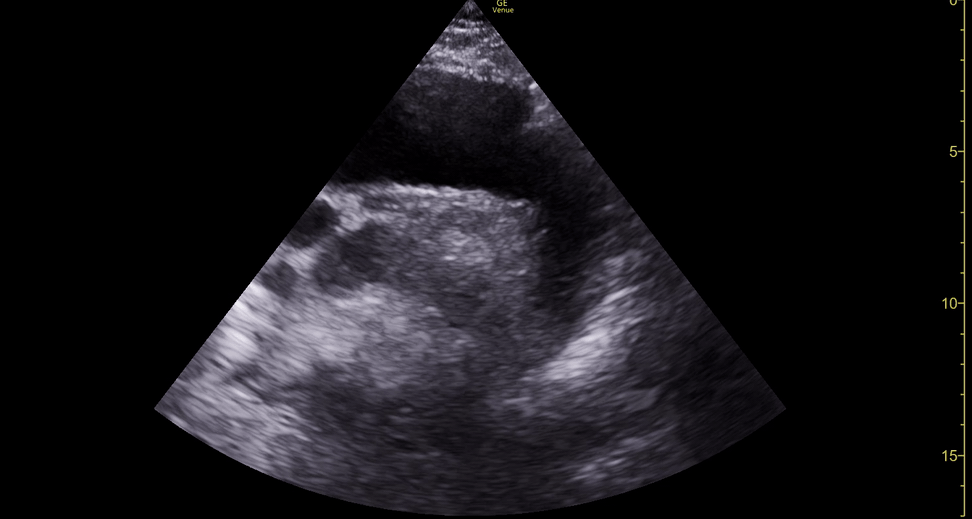

Equality: is the RV dilated or significantly impaired?

Normally, the RV is a low-pressure, thin-walled, high-compliance chamber that wraps anteriorly around the muscular, cone-shaped LV. The normal RV : LV diameter ratio is 0.6 : 1.

When the pulmonary artery pressure rises, the RV will dilate, altering the normal RV:LV ratio. Although sacrificing sensitivity, the use of equality (1:1 ratio) as a cutoff can achieve a specific estimation of RV strain. If imaged correctly by a trained operator, the presence of an RV:LV ratio > 1 is highly specific for RV strain.

RV dilation can be acute, chronic, or acute-on-chronic. However, in patients presenting with undifferentiated chest pain, shortness of breath, hypotension or syncope, the presence of any RV dilation should raise suspicion for acute pulmonary embolism (PE). Furthermore, in a patient in shock, the presence of RV strain may signal the need for aggressive therapy – emergency thrombolysis.

THE VIEWS

The A4C view provides an accurate chamber size comparison. However, achieving a proper A4C view (avoiding foreshortening or ballooning, and visualising the four chambers with a vertically oriented interventricular septum) can be a challenging exercise of image acquisition. Additionally, the PSAX view at the level of the papillary muscles shows both LV and RV side by side and is useful to assess function and size. When RV pressure is high, the septum will be pushed and flattened towards the LV, resulting in the characteristic “D-shaped” LV or “D sign”.